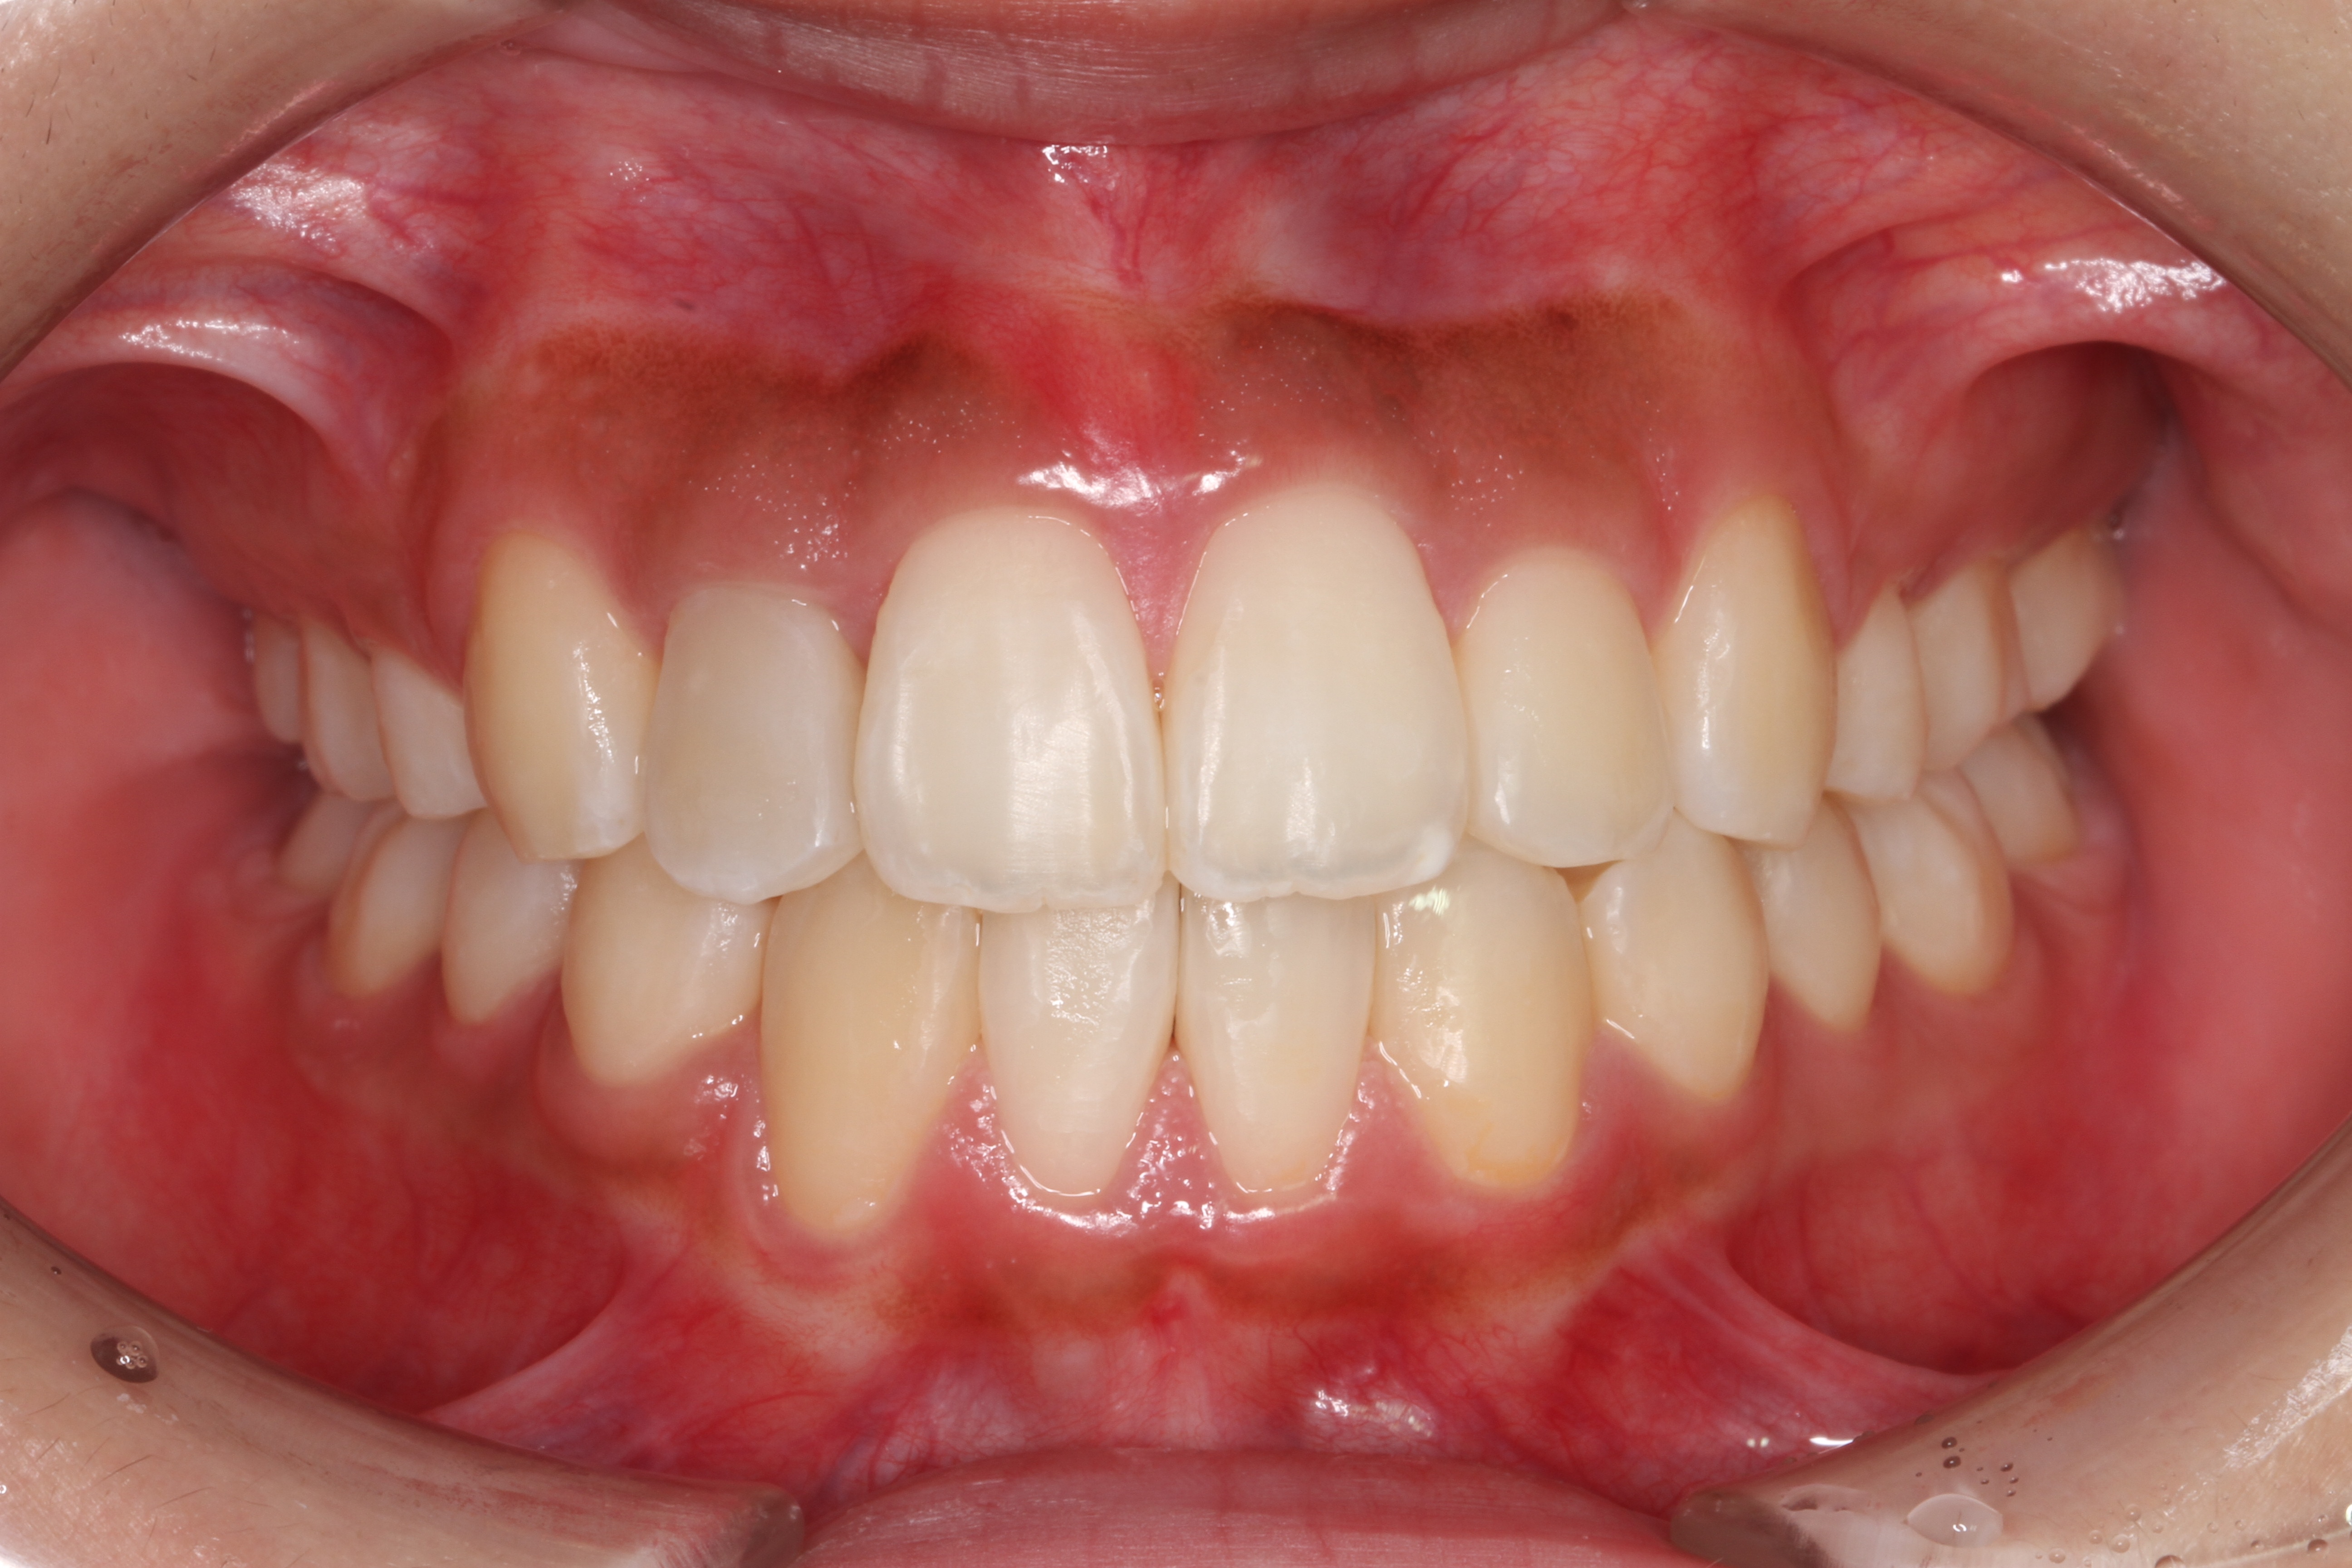

- 患者様情報30代 女性

- 来院動機歯並びが気になる

- 治療内容矯正治療

- 治療期間約2年

- 治療費用1,109,900円(税込)

検査費、治療費、月々の調整費込 - 治療のリスク歯肉退縮の可能性がある、装置装着の痛みを感じる場合がある